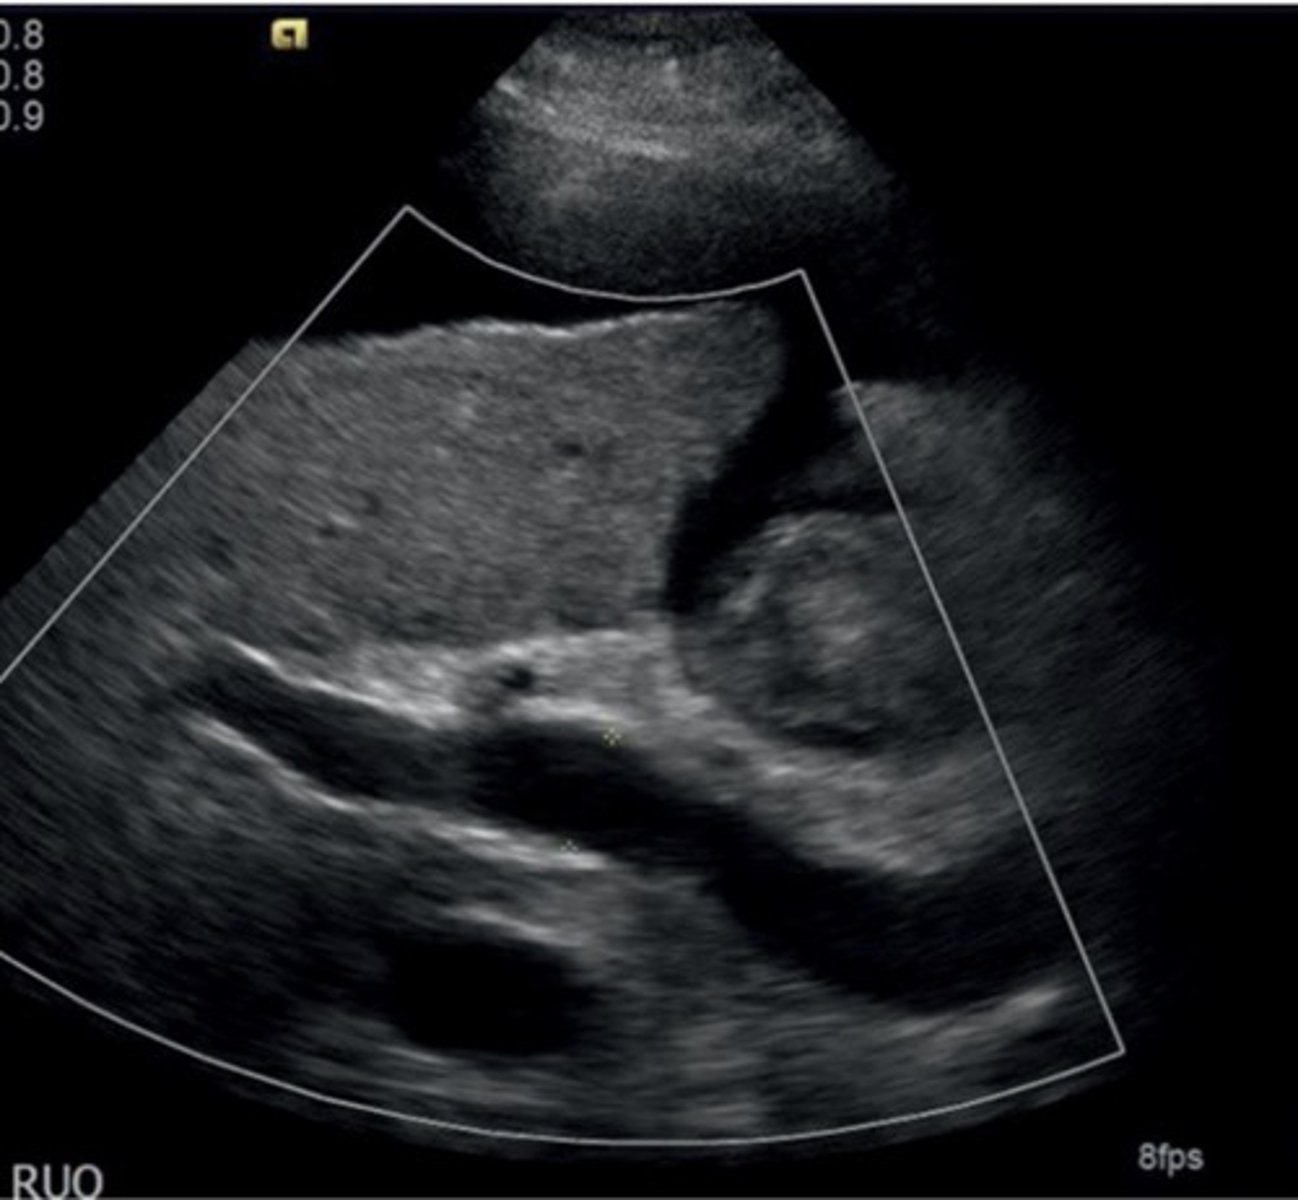

Portal HTN 2D Findings

Large pulmonary vein

Collaterals

Splenomegaly

Ascites

Enlarged hepatic artery